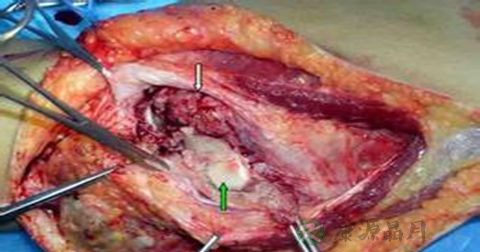

1、咯血:肺结核咯血原因多为渗出和空洞病变存在或支气管结核及局部结核病变引起支气管变形、扭曲和扩张。肺结核患者咯血可引起窒息、失血性休克、肺不张、结核性支气管播散和吸入性肺炎等严重合并症。

2、咯血者应进行抗结核治疗,中、大量咯血应积极止血,保持气道通畅,注意防止窒息和出血性休克发生。一般改善凝血机制的止血药对肺结核大咯血疗效不理想。脑垂体后叶素仍是治疗肺结核大咯血最有效的止血药,可用5~10U加入25%葡萄糖40ml缓慢静注,持续10~15min。非紧急状态也可用10~20U加入5%葡萄糖500ml缓慢静滴。对脑垂体后叶素有禁忌的患者可采用酚妥拉明10~20mg加入25%葡萄糖40ml静注,持续10~15min或10~20mg加入5%葡萄糖250ml静滴(注意观察血压)。近年支气管动脉栓塞术介入疗法治疗肺结核大咯血收到近期良好的效果。